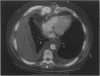

This report describes a late, near-fatal rupture of a false aneurysm of the right internal mammary artery subsequent to coronary artery bypass grafting. The patient presented to us in shock due to hemorrhaging, 8 weeks after bypass surgery that had been complicated by sternal fracture, dehiscence, and infection. Emergent thoracotomy and suture ligation controlled the hemorrhage. To the best of our knowledge, this is the 1st reported case of late massive hemorrhage caused by injury to an internal mammary artery after sternotomy. The literature is reviewed and discussed.